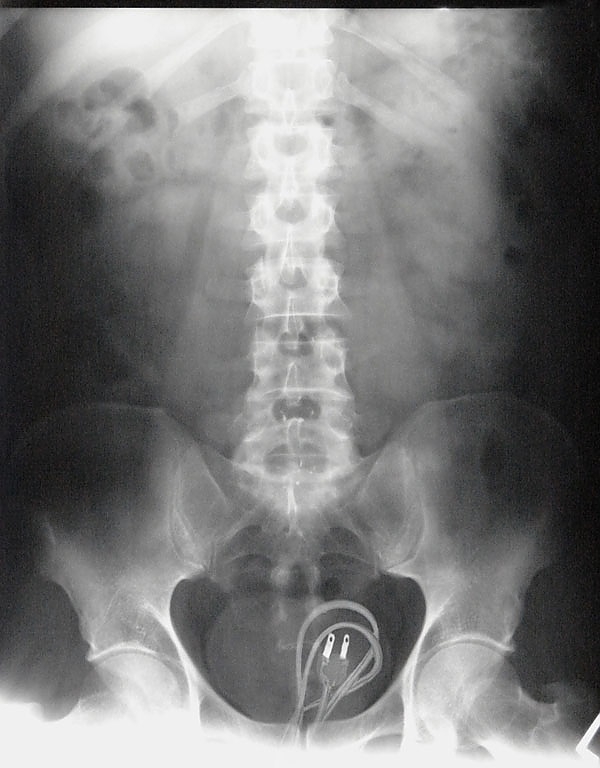

Malum Bölgelerine Kazayla Giren Nesneler Sonucu Acile Kaldırılmış İnsanların 15 Röntgen Görüntüsü  Bu nesnelerin orada olmasının mantıklı hiçbir alakası yok. Büyük ihtimalle bir kaza sonucu bu durum oluşmuştur. Aksini düşünmek bile istemiyorum. Foto Galerimizin devamını görmek için Lütfen sonraki sayfaya geçiniz..